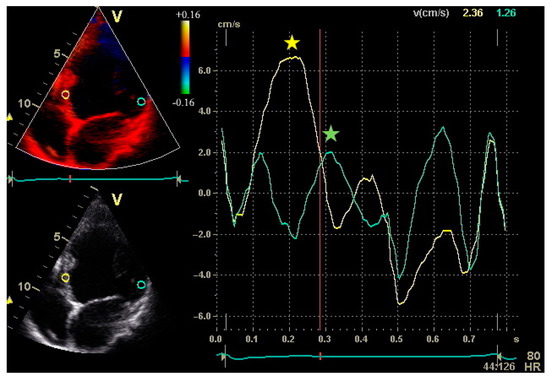

2.1. Assessment of LV Function and Dyssynchrony

- Delgado, V.; Ypenburg, C.; van Bommel, R.J.; Tops, L.F.; Mollema, S.A.; Marsan, N.A.; Bleeker, G.B.; Schalij, M.J.; Bax, J.J. Assessment of left ventricular dyssynchrony by speckle tracking strain imaging comparison between longitudinal, circumferential, and radial strain in cardiac resynchronization therapy. J. Am. Coll. Cardiol. 2008, 51, 1944–1952. [Google Scholar] [CrossRef]